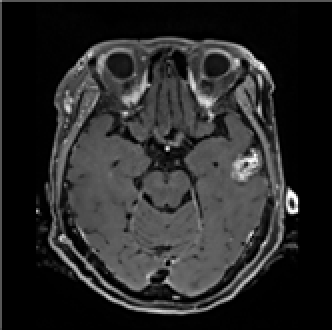

뇌전이암의 조영증강 뇌 MRI를 중심으로 뇌 CT 및 MRI를 이용하여 뇌전이암의 정확한 위치와 크기를 인식하기 위한 AI 시스템을 학습 시킬 수 있는 데이터셋 구축이 목표임

◦ AI 기반 뇌전이암 진단을 위한 다중모델 뇌 영상 데이터 구축 ◦ 뇌전이암 환자의 방사선 치료 설계 보조 인공지능 개발 활용

데이터 설명서 다운로드 구축활용가이드 다운로드구분 내용 구축목적 병변 검출(Detection), 영역 분할(Segmentation) 라벨링 방법 폴리곤 데이터 종류/형식 • 원천 데이터: 영상 DICOM (확장자: dcm)

• 라벨 데이터: JSON, CSV클래스 수량 1종 데이터 실제 예시 • 원천 데이터

Enhaced T1 MRI• 라벨 데이터